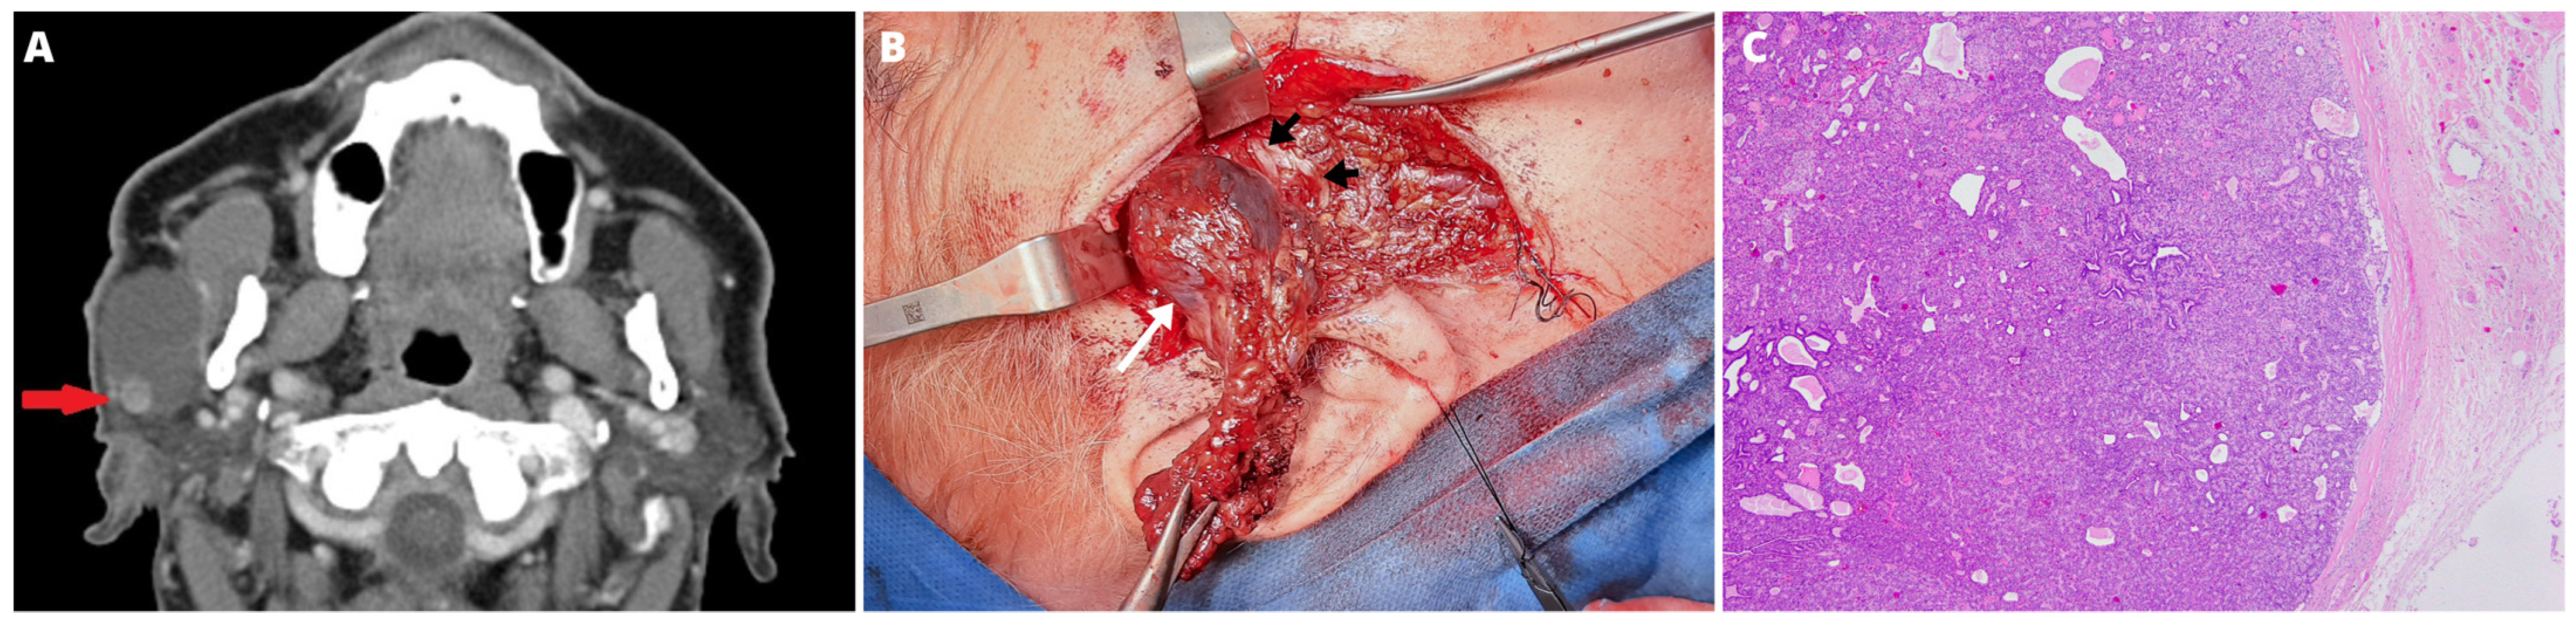

2. Case Report

2.1. Surgery

2.2. Pathology